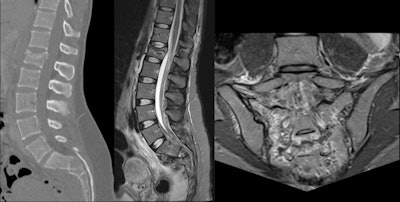

Thoracolumbar spine injuries are more common than cervical spine or sacral lesions. Anterior thoracolumbar abnormalities are a result of excessive loading of the spine, which increases when the athlete is flexed forward. Because elite skiers begin training at an early age, it is likely that the anterior endplate lesions are a result of an imbalance between the applied load and the loading capacity of the immature spine.

CT of the spine highlights fractures and dislocations, raising suspicion of ligament and spinal cord injuries, but MRI has superior sensitivity for these injuries and can confirm soft tissue lesions, vertebral canal hemorrhages, and spinal cord injuries.

Spinal injuries rank as the third most common, after head and abdominal injuries, for critical injuries among patients with severe skiing lesions. They account for between 1% and 13% of all skiing and snowboarding injuries, and peripheral nerve injuries constitute less than 1% of reported cases.

"Spinal injuries are a major cause of permanent disability and appear to be increasing among skiers and snowboarders," the researchers said. "Spinal injuries in skiers have been traditionally much less common than in snowboarders, but this disparity is likely to diminish with the recent trend of incorporating snowboarding moves into skiing."